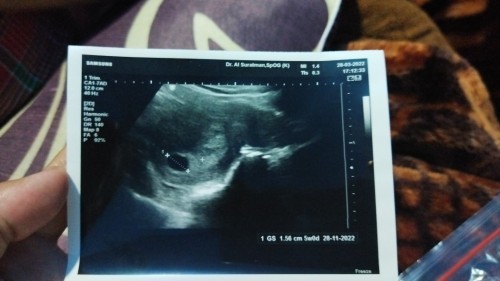

tunggu sampai 12 week bun, minum vitamin & jangan kecapek.an aku 11week baru ada janinnya 8week blum ada, kantungnya jg ukurannya sama 1.56cm itu kantungnya masih 1.56cm masih ada kemungkinan janin berkembang nanti bun, kata dokterku BO itu kalau udah 10-12week dan kantungnya malah membesar 2.5cm

itu diprint an USG nya 5 Minggu Bun. 8 Minggu hitungan berdasarkan HPHT ya ? sebaiknya ikutin yg di USG aja bun. kalo usia kandungan 5week wajar kok baru keliat kantungnya aja

Di kertas hasil usg tertulis masih 5w bund jadi wajar kalau belum terlihat jelas dulu saya sudah terlihat janin dan terdengar djj waktu usia 8w

itu hasil usgnya msh 5week. wajar baru kebentuk kantong yg isi air ketubannya aja. nanti di cek 2 atau 3 minggu lagi kalau berkembang pst sdh terlihat janinnya

Sprtinya itu hasil usg usia 5week bun wjar kemarin wktu q usia sgto keliatan kantung aja trs usg 9 week alhamdulillah suda ada janin n detak jantung nya

keterangan usg nya bru 5minggu bun, normal aja klo msih klihatan kantungnya aja, tnggu sebulan lg insyaallah sdh ada janin & detak jantung bun, Amin